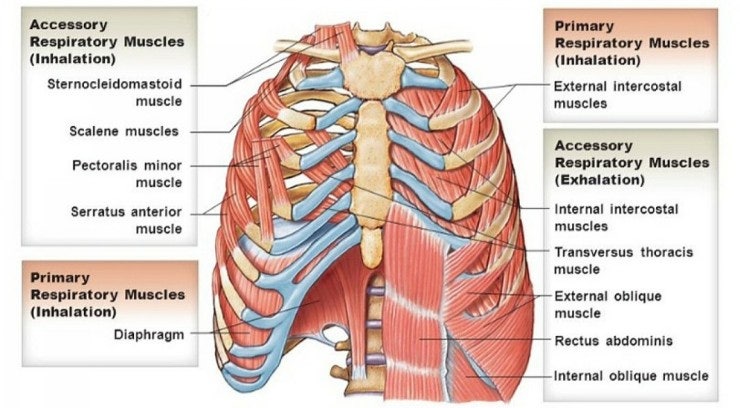

여기서 발가락이 앞으로 내려가 있다면 폐도 나쁜 사람입니다.